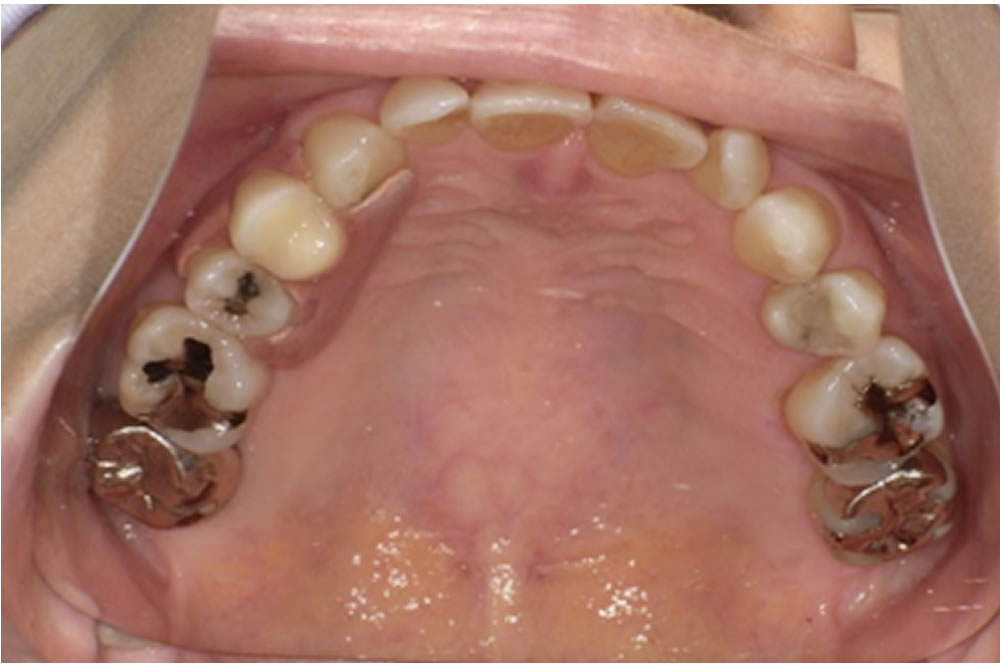

これらの点を踏まえ、最終的に選ばれたのがミラクルデンチャーでした。外科的処置を伴わず、歯を削ることもなく欠損部を補えること、そして審美性が高いこと、清掃がしやすいことなどが主な理由です。ミラクルデンチャーは特殊な「キーとロック」に似た構造によって高い維持力を発揮するため、最初は取り外しに少しコツが必要ですが、慣れると外れにくく快適に使用できるという特徴があります。

義歯の設計では、口腔内の形態に合わせて、床の前方を小さく・後方を大きめにするなど細かな工夫を行い、装着時の違和感が少しでも軽減されるよう調整しました。

製作したミラクルデンチャー

| 治療費用 | ミラクルデンチャー フィット3 右上4 220,000円(税込) |

| 治療期間 | 上顎義歯 2ヵ月(4回) |